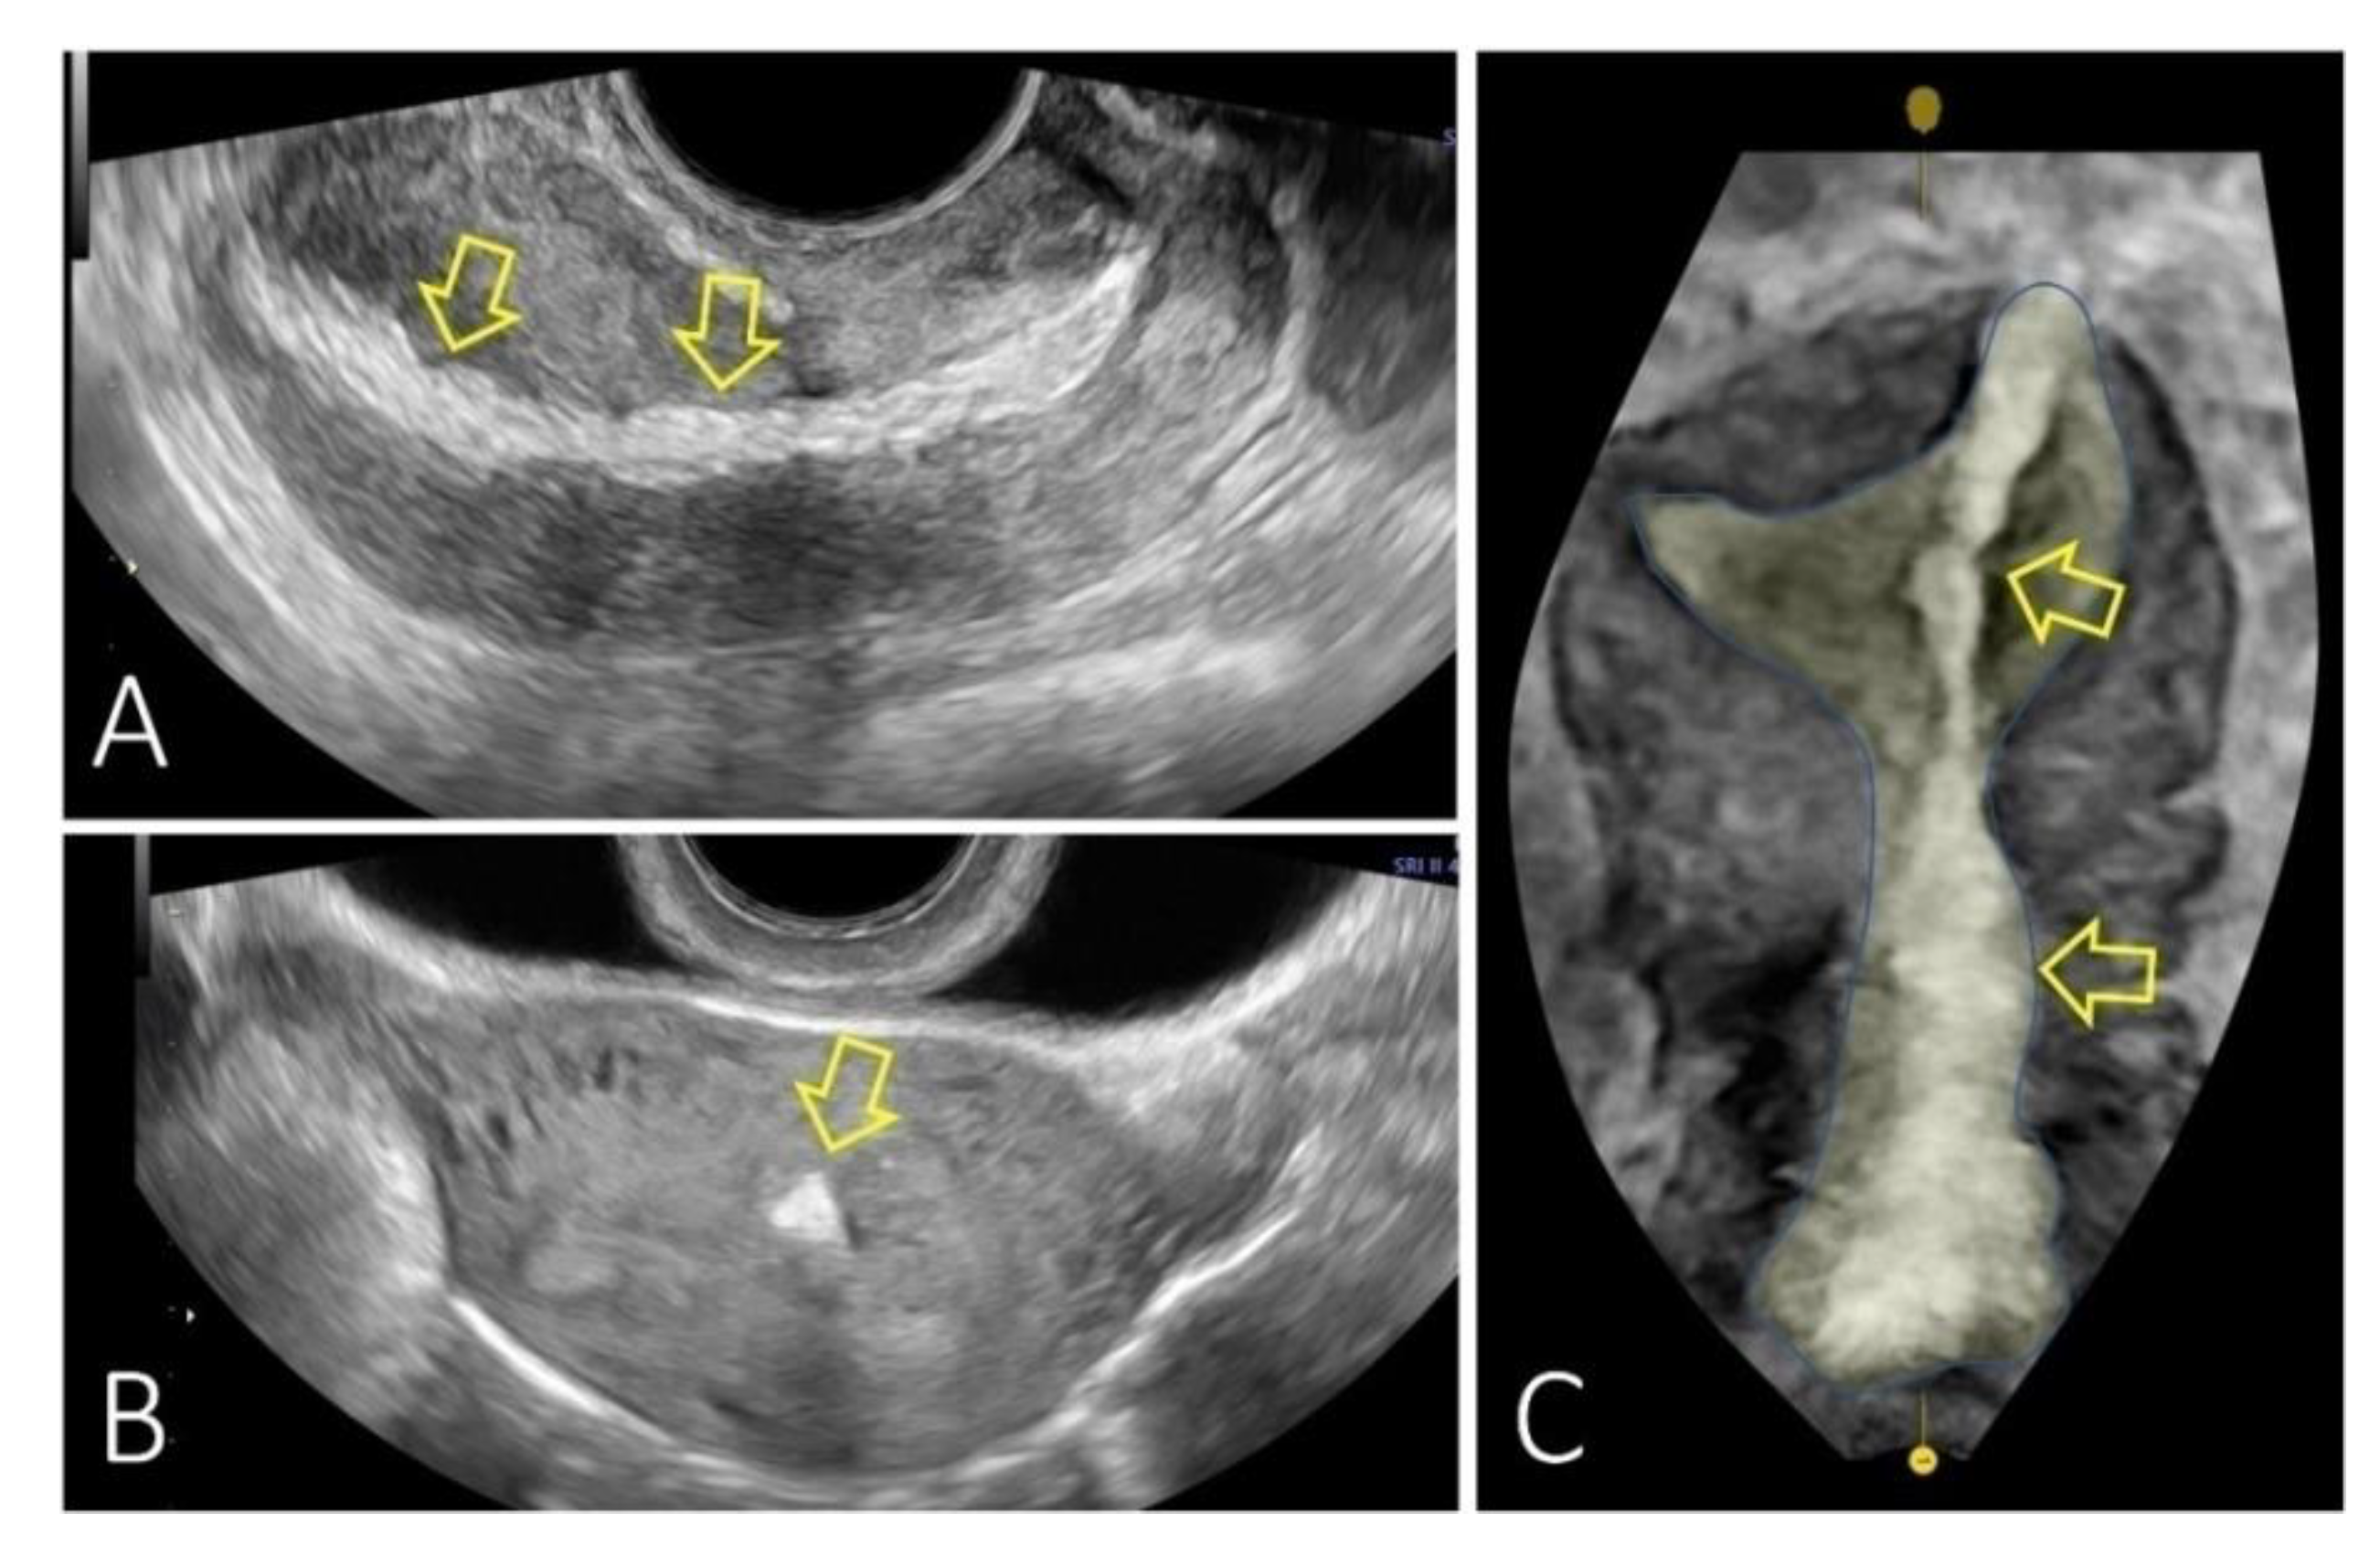

Discover effective options for eardrum perforation repair. Learn how modern medical treatments, including tympanoplasty, can restore hearing loss and heal a ruptured eardrum. Our comprehensive guide covers causes, symptoms, and the recovery process for successful ear drum surgery, ensuring you understand the steps needed to restore your middle ear health and prevent potential infections today.